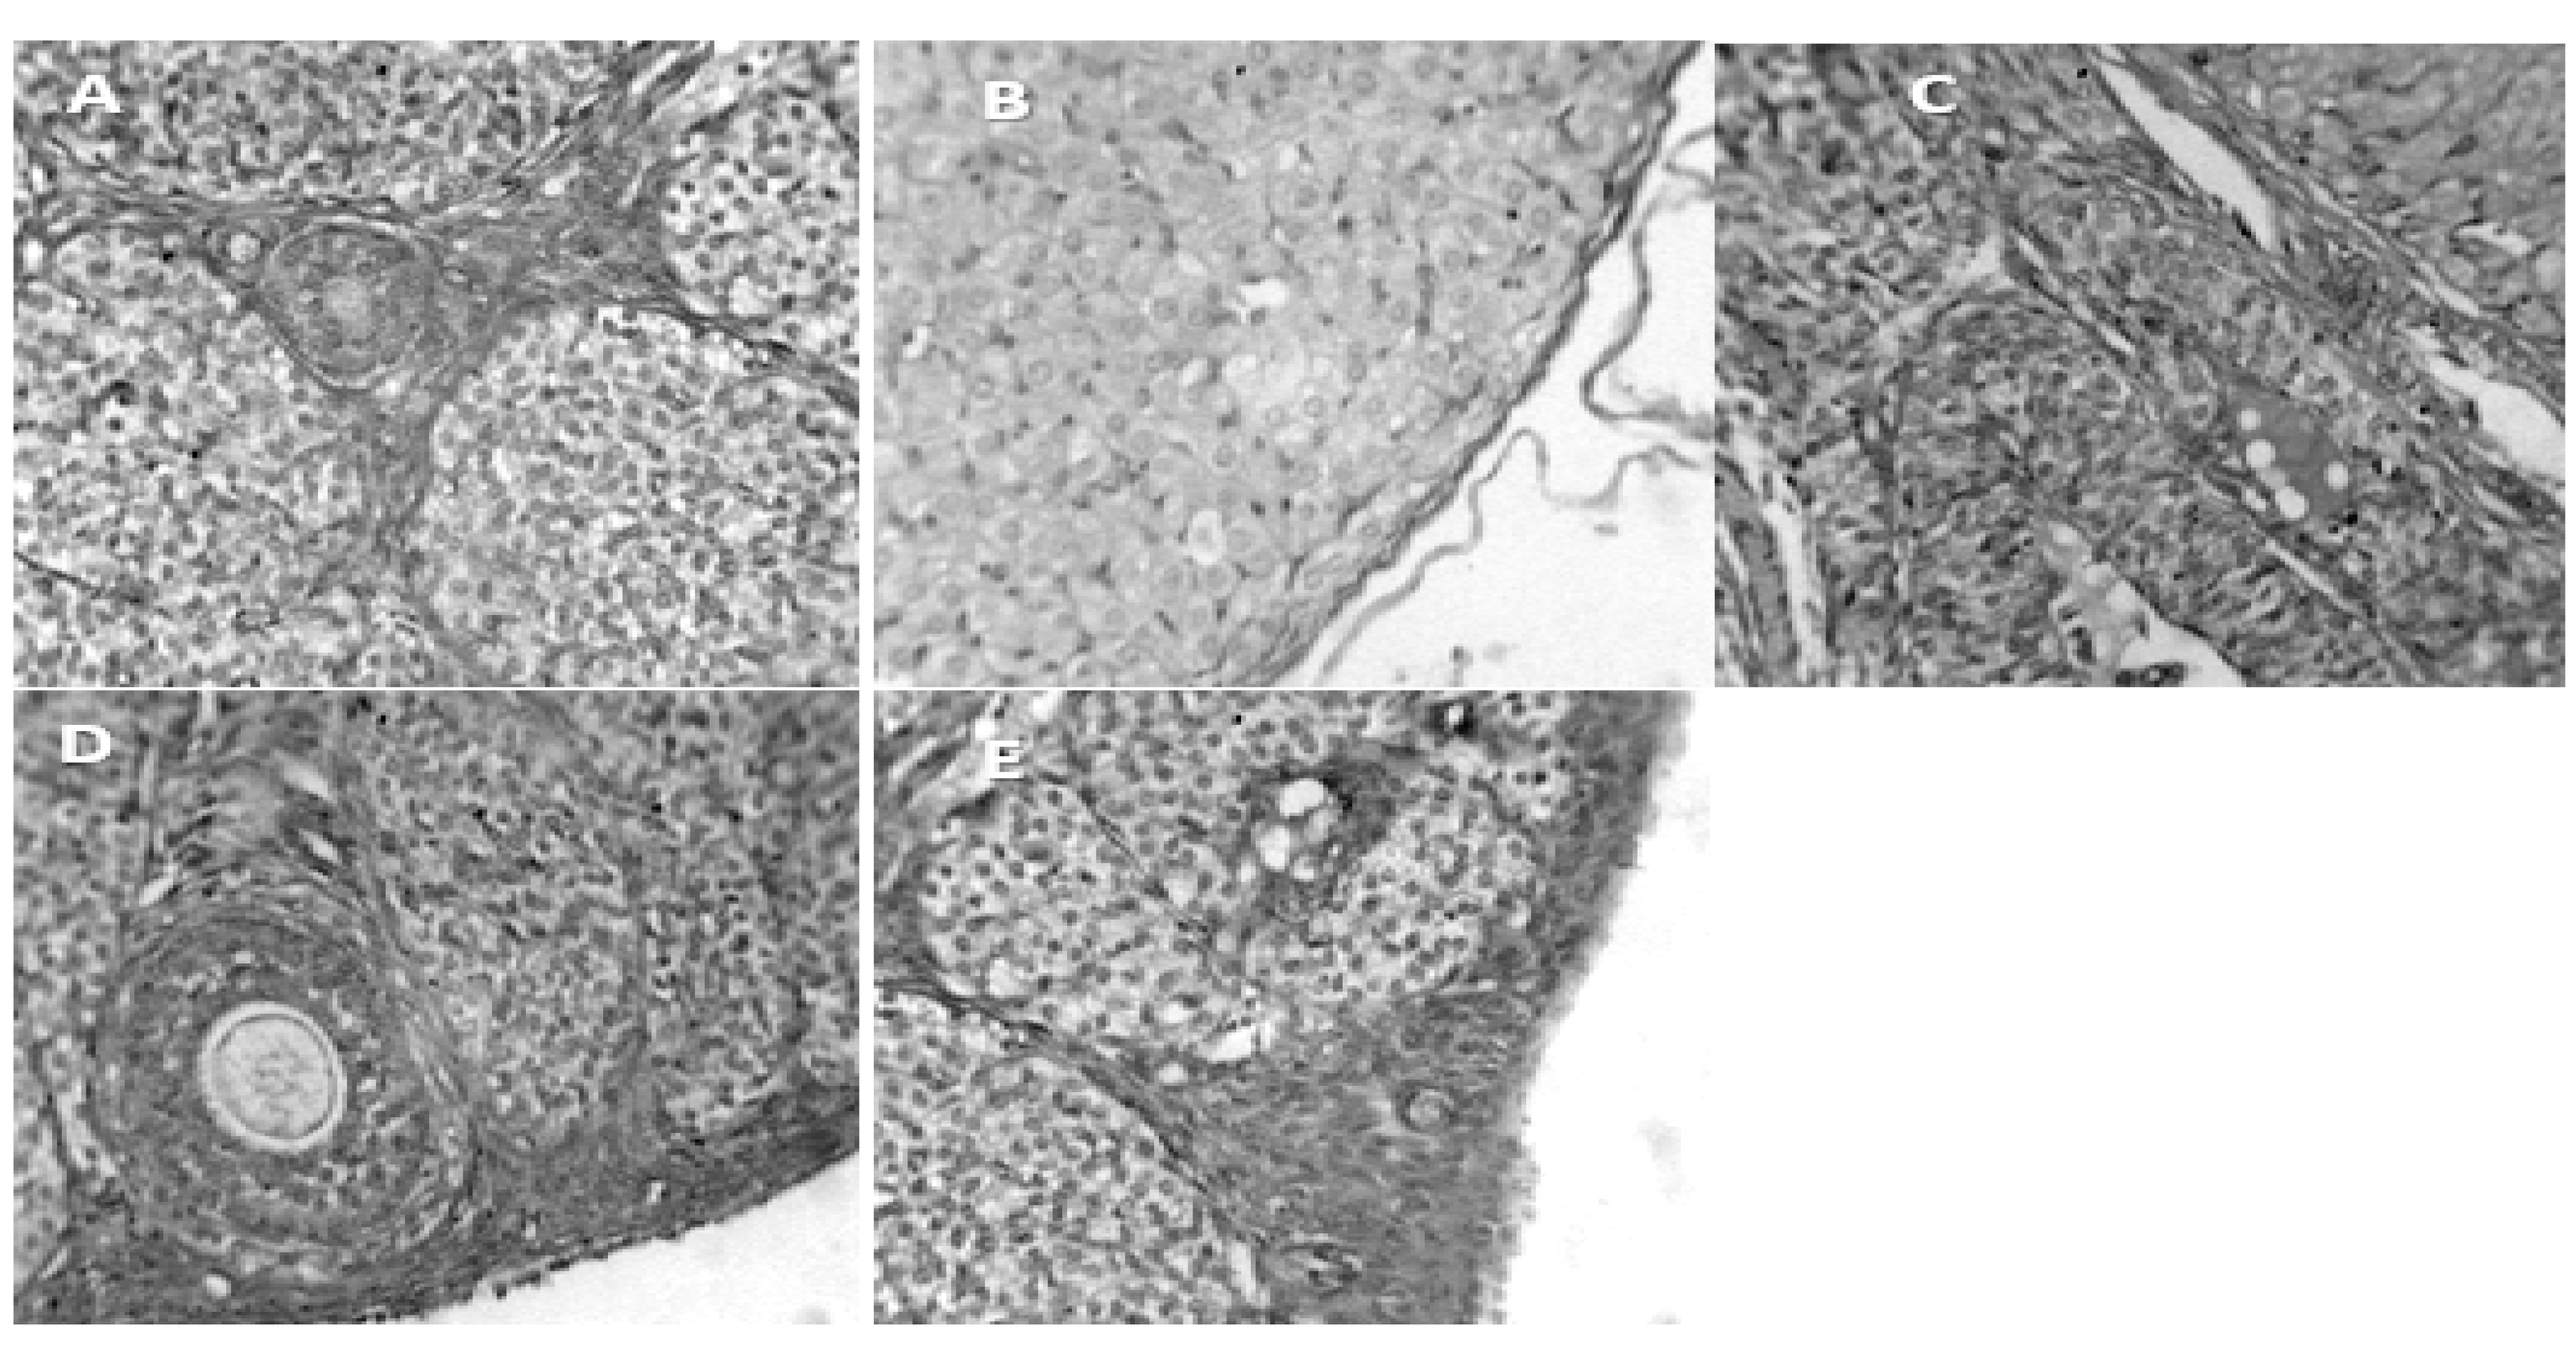

- A.

- Group 1 (Positive Control): Ovaries at different developmental stages, with normal histological architecture

- B.

- Group 2. (Negative Control): Shows diminished number of developing follicles and increased number of atretic follicles

- C.

- Group 3. (200mg/kg NS-oil + 0.5 mg/kg Cy): Shows distribution of developing follicles, degenerating follicle and a balloon tissue necrosis on the ovarian surface

- D.

- Group 4 (400mg/kg NS-oil + 0.5 mg/kg Cy): Presence of developing primary follicles and distorted ovarian stroma

- E.

- Group 5 (800mg/kg NS-oil + 0.5 mg/kg Cy): Shows ovary with follicles at different stage of development, and mild necrosis on the surface